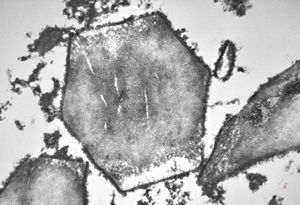

M,58y. | crystalline inclusions in hepatocyte after unknown medication

M,58y. | crystalline inclusions in hepatocyte after unknown medication